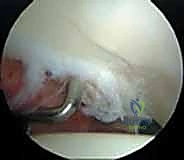

* إصلاح الشفا الحقي (Labral Repair): إذا كان الشفا ممزقاً ولكن نسيجه لا يزال جيداً، يتم إعادة تثبيته في حافة الحُق باستخدام خطاطيف صغيرة جداً (Suture Anchors) تزرع في العظم وتمرر خيوطاً قوية لربط النسيج الممزق.

* تنظيف الشفا (Labral Debridement): إذا كان النسيج الممزق تالفاً جداً ولا يمكن خياطته، يتم تشذيبه وإزالة الأجزاء المتهتكة لتخفيف الألم ومن